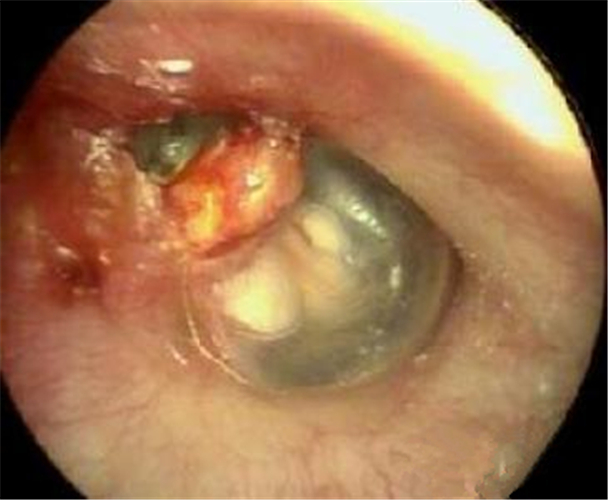

中耳炎鼓膜穿孔